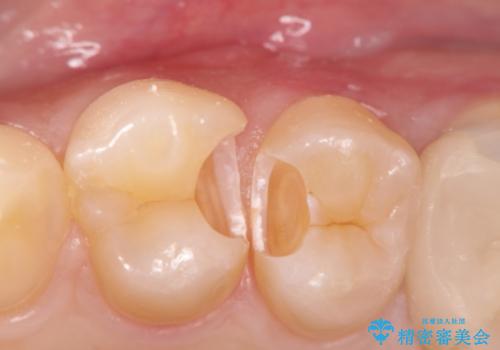

精密なむし歯の治療 セラミックインレー

- 定期健診にてむし歯を認めた患者さまです。

笑った時に見える部分だったためセラミックインレーにて修復しました。

保険治療で使える材料には制限があり、見た目だけでなく精度でも劣ります。当院でのセラミックインレーは歯とのつなぎ目を拡大鏡で確認して精度高く仕上げるため、むし歯のリスクを限りなく少なくできるよう治療します。